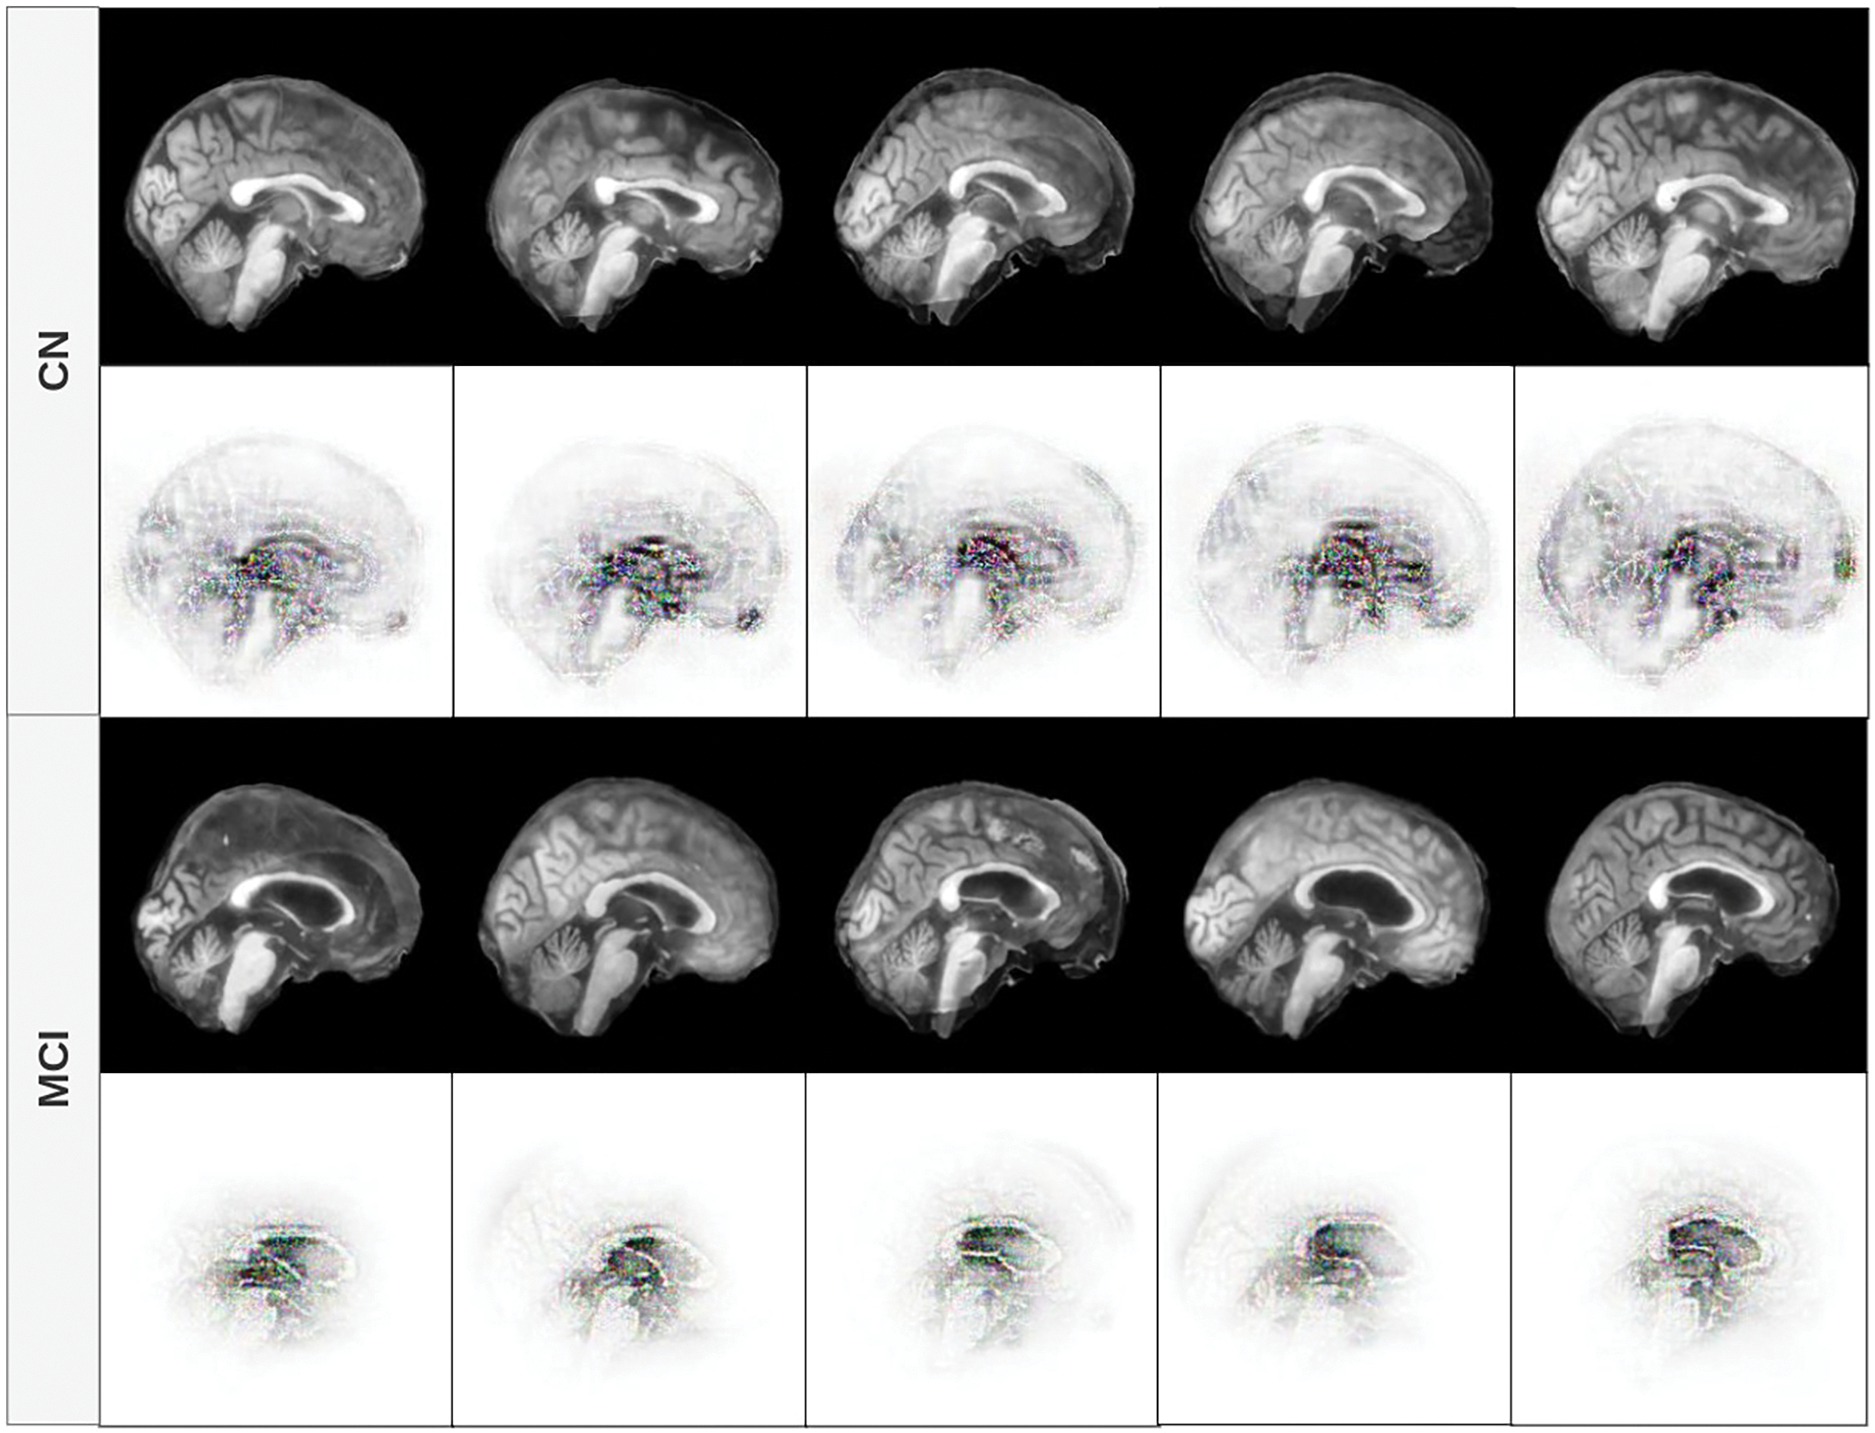

The figures in this subsection present selected visualizations of the most contributing features in different orthogonal planes–sagittal, coronal, and axial–using fused T1w and PiB-PET images. These visualizations help uncover spatial patterns that differentiate CN individuals from those with MCI and are aligned with known clinical markers of early cognitive decline.

Fig. 5 displays the feature contribution maps for the sagittal plane. For MCI subjects, the most notable features are concentrated around midline structures such as the corpus callosum, the thalamus, and the lateral ventricles. These areas are consistent with clinical observations that report structural and metabolic changes in these regions in the early stages of cognitive impairment [55–58]. In subjects with CN, while attention is still partially focused in the brain’s core, the model also focuses on the curvature and width of the cerebral cortex, suggesting a role for cortical thickness and brain volume - both recognized as valuable indicators in neurodegenerative processes.

Figure 5: Feature contribution visualization in the sagittal plane. The model highlights midline brain structures (corpus callosum, thalamus, ventricles) for MCI subjects, while CN cases emphasize cortical curvature and volume

In Fig. 6, we observe that the focus of the model for patients with MCI remains concentrated in the central region of the brain, particularly the lateral ventricles and surrounding white matter. This aligns with the findings that ventricular enlargement and white matter changes are early biomarkers of MCI. For CN cases, the model continues to focus on both central structures and peripheral cortical boundaries, again indicating that preserved cortical morphology is a distinguishing feature in cognitively normal aging [59].

Figure 6: Feature contribution visualization in the coronal plane. The model’s attention for MCI subjects centers around the lateral ventricles and white matter, while for CN cases, it also includes cortical boundaries and overall brain shape